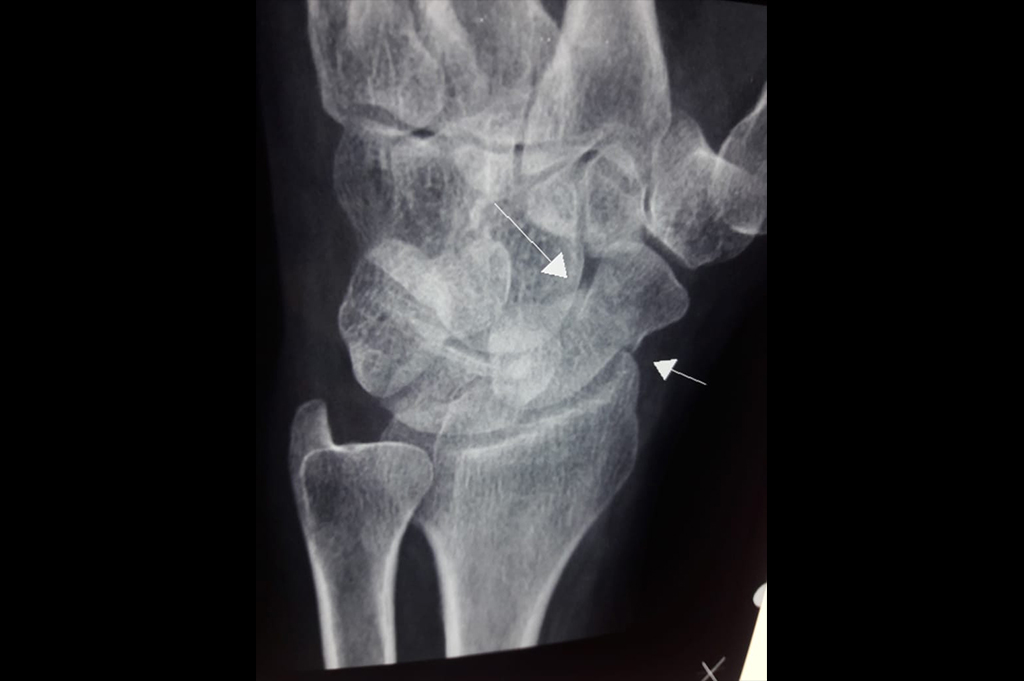

Scaphoid